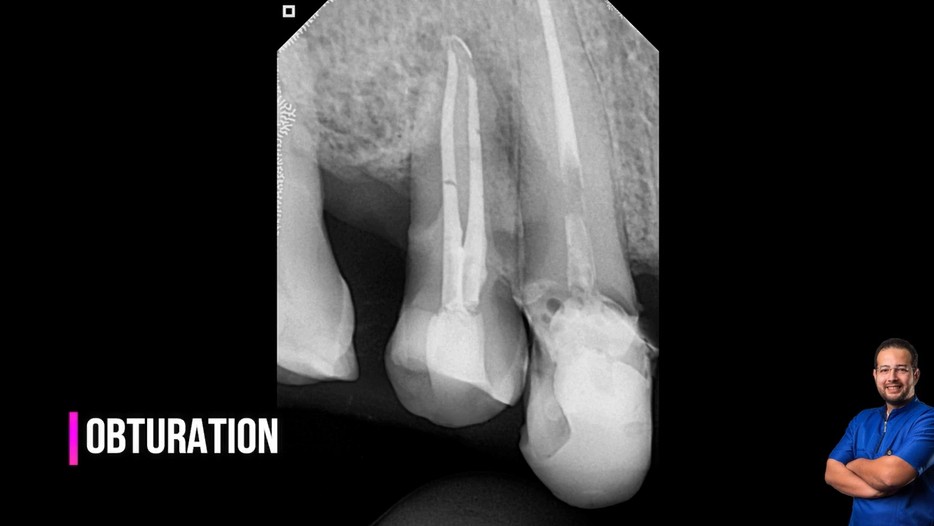

Treatment case sharing from dr wael